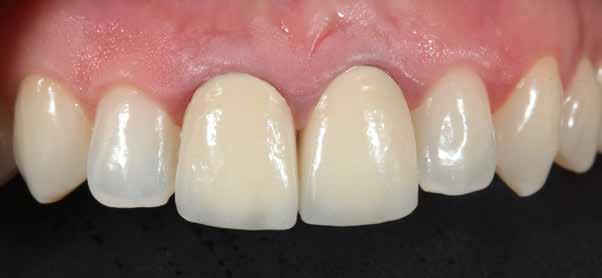

hatékonyságát nagymértékben növelhetjük azáltal, csak zománcon belül preparáljuk, és a kerámia héjaesetismertetésünknek az volt a célja, hogy bemutassuk, kofferdám izolálással megelőzni a munkaterület nyállal, szulkusz-váladékkal történő kontaminációját.

A szakirodalomban fellelhető eredmények alapján kerámia héjak ragasztására a kontaminációtól mentes, frissen vágott zománc felszín a legalkalmasabb. A hosszú távú sikeresség elérésének további feltétele a fogak konzervatív módon történő preparálása, továbbá a ragasztás kofferdám felhelyezésével biztosított, abszolút izolálásban történő kivitelezése. Úgy véljük, hogy a fenti faktorok biztosították a cikkben bemutatásra kerülő esetek – 5 évvel az átadás után megfigyelhető – sikerességét. A kofferdám izolálás alkalmazása számos előnyt biztosít a gyakorló fogorvos számára. Megakadályozza a munkaterület nyállal, vérrel, vagy szulkusz-váladékkal történő kontaminációját, és javítja a kezelendő területre való rálátásunkat. A fogak kerámia héjak ragasztása előtt történő izolálása azonban gyakran kihívást jelenthet a kevesebb klinikai tapasztalattal rendelkező fogorvosok számára. Jelen esetbemutatásban ismertetjük a kofferdám felhelyezésének lépéseit és néhány olyan gyakorlati tanácsot, amelyek jelentősen megkönnyíthetik a munkánkat, azokban az esetekben, amikor a második kisőrlőfogak közti területet kívánjuk kofferdám segítségével izolálni. A kofferdám kapcsok segítségével került rögzítésre, majd fogakat körülvevő széleit óvatosan az ínybarázdába forgattuk. A kerámia héjak számára előkészített fogakra ragasztás előtt egyenként kapcsokat helyeztünk annak érdekében, hogy a kerámia héjak rögzítése ideális körülmények között történhessen. A lépések részletes ismertetése segítséget jelenthet – a kevesebb klinikai tapasztalattal rendelkező fogorvosok számára – az abszolút izolálás megvalósításához szükséges lágyrészmenedzsment megértéséhez. Ezek az ismeretek rendkívül hasznosak lehetnek, ha a jövőben a kerámia héjak ragasztását megfelelő módon megvalósított kofferdám izolálás mellett kívánják kivitelezni. A cikkben ismertetett módszerek alkalmazásával az abszolút izolálás megvalósítható, a gumilepedő – vérzés nélkül – ínybarázdába történő beforgatására, és a ragasztáshoz szükséges idő csökkentésére.

Az oxigén inhibíciós réteg kialakulásának elkerülése érdekében a kerámiafelszíneket glicerin géllel (Liquid Strip, Ivoclar Vivadent, Schaan, Liechtenstein) borítottuk, majd ezeket a felszíneket ismét 20-20 másodpercen keresztül világítottuk. A végeredmény megfelelt a páciens esztétikai igényeinek (6. a. ábra). Az átadott restaurátumok épségének megőrzése érdekében, a páciens számára éjszakai fogvédő sín készült. Az ötéves kontroll alkalmával megállapítottuk, hogy az elvégzett kezelésünk továbbra is sikeresnek tekinthető (6. b. ábra)

Az általunk alkalmazott adhezív rendszerek hatékonyságát nagymértékben növelhetjük azáltal, hogy a fogakat minimál invazív módon, azaz csak zománcon belül preparáljuk, és a kerámia héjakat kofferdám izolálásban ragasztjuk. Jelen esetismertetésünknek az volt a célja, hogy bemutassuk, hogyan lehet az adekvát módon kivitelezett kofferdám izolálással megelőzni

a munkaterület nyállal, vérrel vagy szulkusz-váladékkal történő kontaminációját. A megfelelő méretben kialakított perforációs nyílások és köztük lévő optimális távolság elengedhetetlen ahhoz, hogy a kofferdámot ideális módon tudjuk felhelyezni. Ezzel az esettel azt is bizonyítjuk, hogy a gumilepedő levegőfújással, fogselyemmel és teflonszalagok segítségével történő beforgatásával az ínyvérzés kialakulását el lehet kerülni. Ismételten szeretnénk hangsúlyozni, hogy a megfelelő kofferdám kapcsok használata nélkül nem tudtuk volna a preparált csonkszélt a gumilepedő szélétől eltartani. A kezelés során elért eredményeket jól alátámasztotta, hogy a páciens az ötéves kontroll vizsgálat során teljesen elégedett volt.